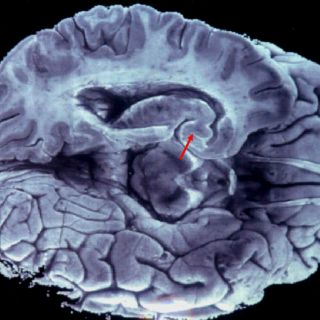

Millones de fibras conectan una mitad y otra del cerebro de mamíferos, que juntas forman el cuerpo calloso y transmiten información esencial para que los dos hemisferios cerebrales puedan comunicarse entre sí, señala el CNB en una nota.

Si este cableado no se forma bien durante el desarrollo postnatal, los hemisferios funcionarán de manera descoordinada, lo que llevará a la pérdida de las funciones superiores del cerebro y a enfermedades mentales con origen en el desarrollo.